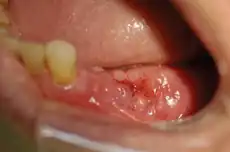

| MRONJ Staging | Criteria* (>8 weeks) | Treatment Strategies** | Picture |

| Stage 1 | Exposed and necrotic bone, or fistulae that probes to bone, in patients who are asymptomatic and have no evidence of infection | Antibacterial mouth rinse, Clinical follow-up on a quarterly basis, Patient education and review of indications for continued bisphosphonate therapy |

|